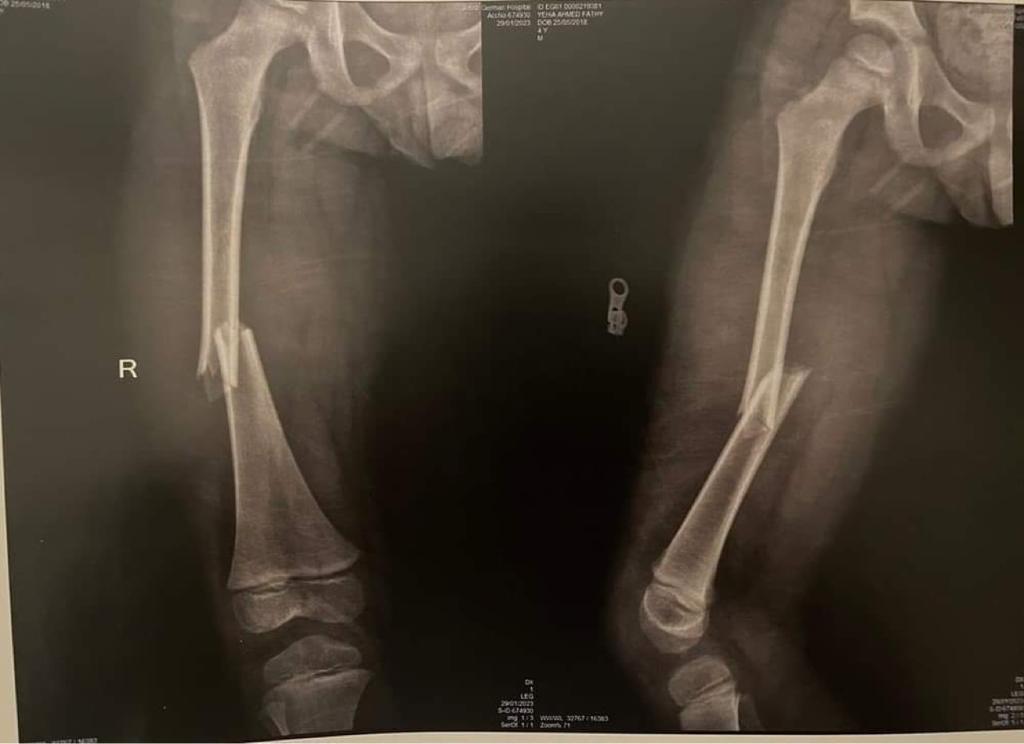

وقال والد الطفل أحمد فتحي لـ القاهرة 24: أصيب الطفل في كسر في الفخذ، وأجريت له عملية تركيب مسامير، وسيبدأ الطفل في رحلة العلاج الطبيعي، وبعد 4 شهور سيتم إجراء عملية أخرى له.

وأخبرت المستشفى والدة الطفل أنه مصاب بكسر في عظمة الفخذ، ويحتاج إلى عملية جراحية، ومن بعدها علاج طبيعي ويحتاج إلى عملية أخرى.